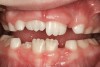

Without esophageal pressure monitoring to demonstrate the increase respiratory effort, bruxism activity may not be recognized as being associated with a respiratory event.71,72 This RERA-related phenomenon was verified in a study of 50 pediatric subjects with an inclusion criteria of sleep-related tooth wear.73 No significant statistical association was found between AHI and the severity of bruxism. However, when respiratory effort–related arousals were added to the AHI, a statistically significant association was found. The bruxing events acted to protect the airway rather than to resolve an obstruction. Bruxism should rise with UARS, habitual snoring, and occasional snoring, because negative pressure and respiratory effort drives the action. The researchers concluded that pediatric sleep-related tooth wear could be used as a marker for SDB. Currently, no other healthcare provider is more equipped to evaluate and monitor pediatric nocturnal tooth wear than the dental practitioner (Figure 21 and 22).

(21.) Six-year-old male presents nocturnal bruxism, habitual snoring, and behavioral issues. PSG reports an AHI of 9.6/hr and respiratory effort–related arousal (RERA) of 14.2/hr (Case provided by Kathy French, DDS).

Figure 21

(22.) Radiograph highlights the obstructed nasal airway preoperatively. Three months after T&A, another PSG demonstrated an AHI of 0.3 and RERA of 0.0/hr.

Figure 22